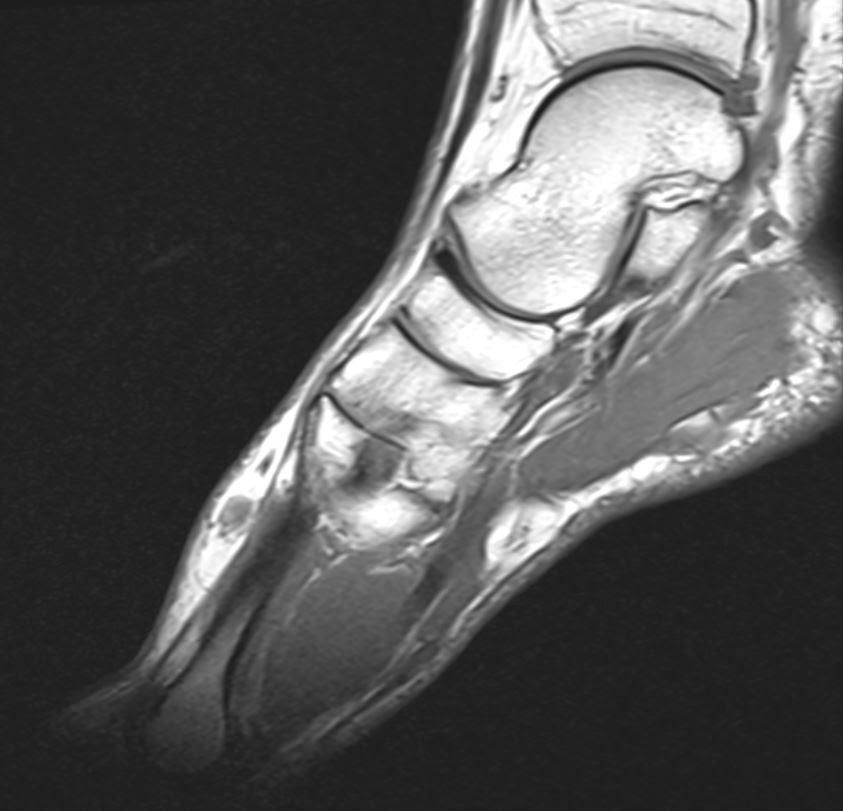

Madura foot an approach to imagingbased diagnosis Eurorad